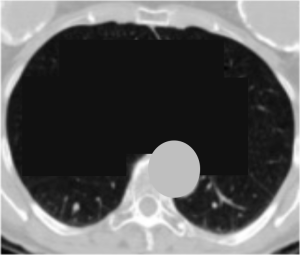

Liu et al. compare their method to the other methods on two datasets. We will focus on the results based on the LIDC dataset which contains annotated CT scans of lung nodules. To test that their method truly enforces causal alignment they add a pseudo-feature to the images:

All the images which contain a malignant nodule get a "+" in the top-left corner. All the images which do not contain a malignant nodule get a "-". A simple model could just look at the top left corner and get the correct answer every single time! But that would have two problems:

- Low alignment score: The simple model would pay attention to the wrong area (the nodule is almost never in the top-left corner)

- Low classification accuracy: The simple model would not be able to classify any images which do not contain the +/- label

Liu et al.'s method should be able to avoid these two problems:

- High alignment score: The model should still pay attention to the nodule, not the +/- label

- High classification accuracy: The model should be able to classify images without the +/- label. Thus, we only provide the +/- label in the training set, not in the test set.